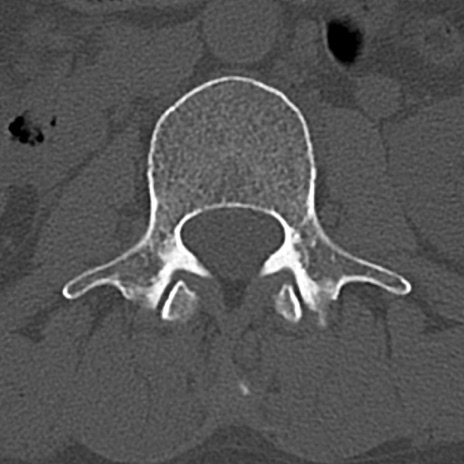

腰椎CT

横断像と矢状断像